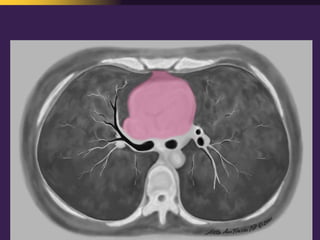

This document discusses mediastinal pathology using a compartmental approach. It describes the anatomy of the mediastinum and divides it into anterior, middle, and posterior compartments. Each compartment contains different structures and has a characteristic distribution of lesions. For example, 50% of lesions occur in the anterior compartment, which contains the thymus. The thymus is the most common site of lesions in the anterior compartment. Thymomas are the most common epithelial tumors of the thymus and mediastinum.